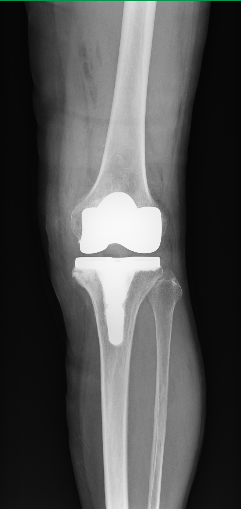

人工膝関節置換術とは?

変形性膝関節症や関節リウマチによる関節の変形によって、痛みや動きにくさなどで日常生活に影響が出てしまった場合に選択される手術方法です。

TKAは、変形した太ももの骨(大腿骨)とすねの骨(脛骨)の関節面を人工の関節に変える手術です。

変形の程度によって、人工膝関節単顆置換術(Unicompartmental Knee Arthroplasty 以下UKA)という手術方法があります。TKAは大腿骨と脛骨の関節面を全部人工関節に取り替えてしまうのに対し、UKAは大腿骨と脛骨のそれぞれ片側だけ(内側がほとんど)を交換する方法です。